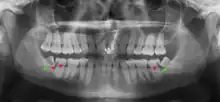

Impacted 2nd molar (red arrow) with developing wisdom tooth (green arrow)

There is no standard to screen for wisdom teeth. It has been suggested, absent evidence to support routinely retaining or removing wisdom teeth, that evaluation with panoramic radiograph, starting between the ages of 16 and 25 be completed every 3 years. Once there is the possibility of the teeth developing disease, then a discussion about the operative risks versus long-term risk of retention with an oral and maxillofacial surgeon or other clinician trained to evaluate wisdom teeth is recommended. These recommendations are based on expert opinion level evidence.[19] Screening at a younger age may be required if the second molars (the "12-year molars") fail to erupt as ectopic positioning of the wisdom teeth can prevent their eruption. Radiographs can be avoided if the majority of the tooth is visible in the mouth.

Coronectomy of impacted wisdom tooth post-op xray showing root remnants (red arrow) and inferior alveolar nerve (green arrow)

Coronectomy is a procedure where the crown of the impacted wisdom tooth is removed, but the roots are intentionally left in place. It is indicated when there is no disease of the dental pulp or infection around the crown of the tooth, and there is a high risk of inferior alveolar nerve injury.[31]

Coronectomy, while lessening the immediate risk to the inferior alveolar nerve function has its own complication rates and can result in repeated surgeries. Between 2.3% and 38.3% of roots loosen during the procedure and need to be removed and up to 4.9% of cases require reoperation due to persistent pain, root exposure or persistent infection. The roots have also been reported to migrate in 13.2% to 85.9% of cases.[31]